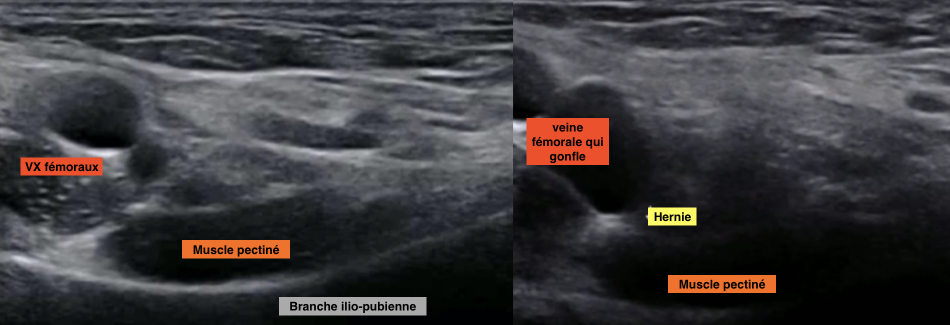

Hernie fémorale

Technique

- Permet de tester le valsalva

- Repères anatomique

- Vx fémoraux

- Muscle pectiné

crural crurale femoral

Test du valsalva

Hernie fémorale